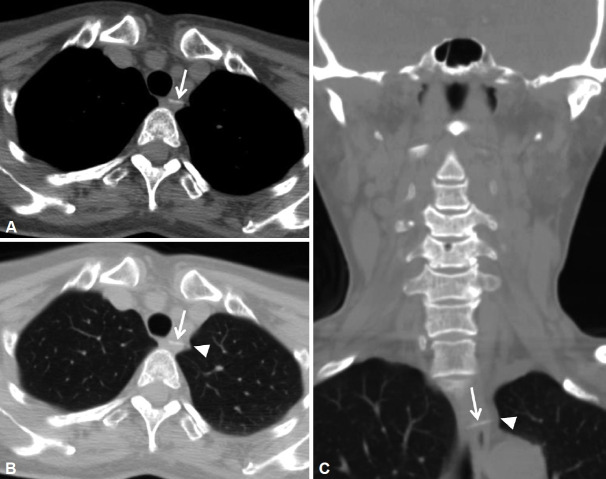

Although most digestive tract foreign bodies pass naturally, approximately 10% require endoscopic removal and another 1% require surgical intervention. The upper esophagus is the most common site of foreign body impaction. In the East, fish bones are the most commonly encountered foreign bodies in the esophagus, whereas in the West, meat is the most common. Prompt removal of these impacted foreign bodies is important because they may lead to serious complications, such as esophageal perforation or obstruction. The esophagus is located in the deepest part of the chest and is in close proximity to vital organs, such as the aorta, heart, lungs, and vena cava. Thus, a sharp foreign body that penetrates the esophagus may puncture nearby organs, potentially leading to a variety of intrathoracic organ complications, including an aortoesophageal fistula, pericarditis, and pneumothorax. Although pneumothorax rarely results from fish bones impacted in the esophagus, we report two cases of characteristic pneumothorax caused by fish bone foreign bodies in the esophagus and provide a review of the associated literature.